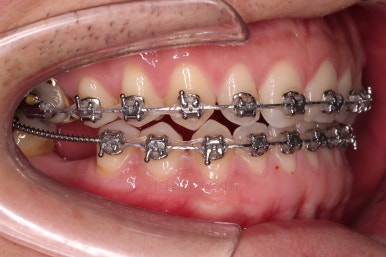

교정치료도 종료 되었고 연산동임플란트 잘 완성이 되었어요.

총 14개월이 걸린 치료였는데 비교적 짧은 기간 내에 틈새도 모으고, 임플란트 및 충치치료도 다 완료를 할 수 있었습니다.

전후 사진을 비교해 볼게요.

비교적 짧은 시간 안에 환자분이 만족하는 치료를 할 수 있었어요.